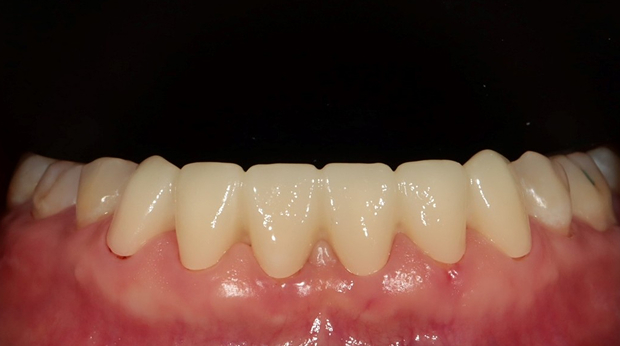

임플란트와 사랑니 발치는 외과적 시술로 잇몸을 절개하는 외과적 시술은

짧으면 짧을 수록 시술 후 붓기와 통증이 최소화됩니다.

치과의사 경력 14년차 구강외과 전문의가 빠르고 안전하게, 아프지 않게 수술해 드립니다.